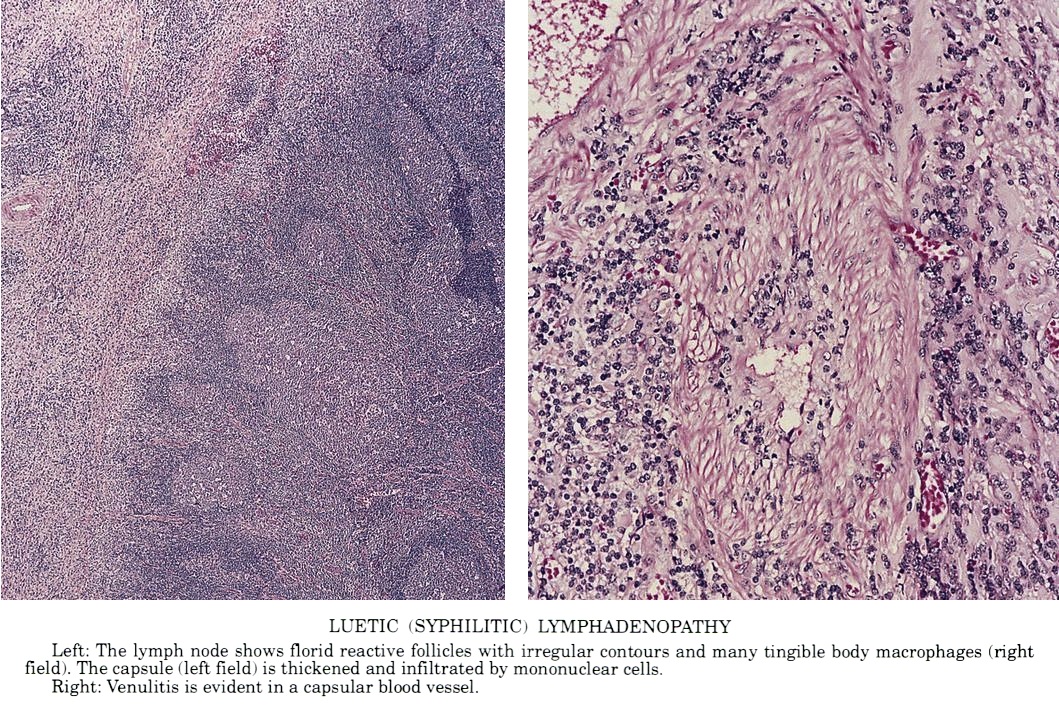

- Lymph node:

- Primary syphilis:

- Capsular and pericapsular fibrosis, follicular hyperplasia, diffuse interfollicular plasma cells, prominent endarteritis outside the capsule

- Noncaseating granulomas and abscesses are rare

- Spirochetes easiest to identify within blood vessel walls

- Secondary / tertiary syphilis: follicular hyperplasia

Microscopic (histologic) images

Contributed by Silvija P. Gottesman, M.D., Hillary Rose Elwood, M.D., Mark R. Wick, M.D. and AFIP images